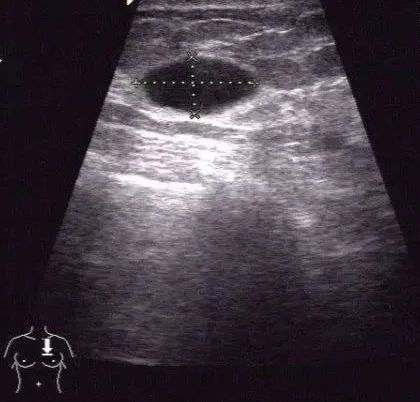

大一些的囊肿患者可能可以自己摸到,张力比较大的囊肿比较好摸到,较软的囊肿很难摸到,需要全自动乳腺超声波检查设备检查发现。

目前大多数囊肿治疗我们采取的是在超声引导下行抽吸术,不需要麻醉。